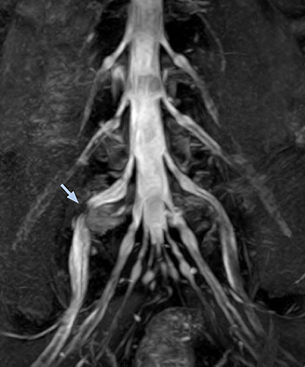

At Northern Fukushima Medical Center in Japan, excellent MRI visualization of nerves helps support confident diagnoses and informs surgical treatment decisions for patients with lower limb symptoms. MRI technologist Tanji and orthopedic surgeon Dr. Yabuki share how direct nerve visualization with the 3D NerveVIEW method adds information when diagnosing atypical herniations. The additional insights changed their way of working and benefit their patient care, as illustrated by some clinical examples.

“In patients with lower extremity neurological symptoms, NerveVIEW helps us to determine the disease matching the patient’s symptoms by directly visualizing the nerves. We use the sequence mainly, when there is suspicion of intraforaminal stenosis, extraforaminal stenosis or lateral disc herniation, which is often based on routine T2- and T1-weighted images. Additionally, the excellent depiction of the course of nerves makes NerveVIEW a good navigator when applying treatment such as block therapy or surgery.”

Northern Fukushima Medical Center (NFMC) Imaging Center uses the 3D NerveVIEW sequence for performing MR neurography, particularly in patients with pain and weakness in the lower limb. “It is included in about 20% of the approximately 150 lumbar spine MRI exams each month at NFMC, and can help us to determine if structures are impinging on the nerves,” says Hajime Tanji, RT, MRI technologist at NFMC.

“In such case, we would then browse through axial T2-weighted MR images slice by slice and mentally reconstruct the actual situation based on both radiculography and MRI. Fortunately, NerveVIEW can now very well show nerve courses and presence of nerve compression or edema in one single image series.” “We have often seen NerveVIEW directly depict details of the nerve compression that were not observed by radiculography. Therefore, we think that with NerveVIEW we can reduce the number of invasive examinations, especially for some patients with lumbar plexus symptoms.”

The key concept in MR neurography, Dr. Yabuki stresses, is the ability to directly visualize spinal nerves, versus inferring the presence of pathology indirectly. “Before NerveVIEW, we estimated compression of the nerve by looking for the presence or absence of fat signal on other MR images,” he says.

“For example, in sagittal images, when the presence of fat is observed in the intervertebral foramen, it suggests that there is a margin around the nerve. Similarly, the absence of fat indicates that the nerve is being compressed. So, we used to deduce nerve compression indirectly. With NerveVIEW, however, we can observe the condition of the nerves directly, regardless of the presence or absence of fat. We always prefer such direct observation of anatomy over having to make an inference about it.”

“NerveVIEW can clearly show nerve courses and presence of nerve compression. However, when multiple abnormalities are seen, it can still be hard to determine which nerve is causing the symptoms,” says Dr. Yabuki. “In our experience so far, we see abnormal findings on NerveVIEW in about 70% of elderly patients. As the pain is usually caused by only one nerve, we thus need to find the exact corresponding nerve.” “With a nerve root block, the patient's pain is improved by infiltration of local anesthesia directly around the nerve root considered to be responsible. Knowing such nerve root block findings prior to image interpretation, helps to easily recognize abnormal findings on NerveVIEW as well. In other words, without a priori knowledge, based on symptoms and/or nerve root block findings, we must be aware of the possibility of overdiagnosis.”

The addition of the nerve-selective NerveVIEW sequence to its spine MRI protocol has given NFMC competitive advantages, according to Tanji. “Since we started including NerveVIEW routinely, the demand for lumbar spine MRI examinations has increased, especially for pre-surgical planning purposes and for patients with chronic lower extremity symptoms,” he says. “Moreover, because no other hospitals in our region are doing nerve plexus imaging yet, we often receive referrals for MR neurography studies from other hospitals even if they have an MRI scanner. Some requests come from as far as 100 km away. NerveVIEW definitely provides us a competitive advantage.” “Based on our experience, we can certainly recommend NerveVIEW to other centers,” Dr. Yabuki adds. “The sequence opens up many possibilities to facilitate the diagnosis of lower extremity pain and to inform our decision-making regarding therapy and surgery.”